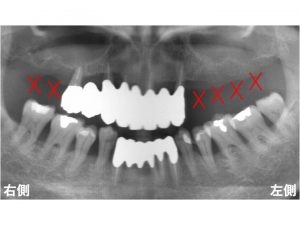

以下は治療前です。

上顎の右側に2歯の欠損、

上顎左側の奥歯が4歯欠損しています。

問題となるのは、この欠損部だけではありません。

上顎の前歯です。

上顎前歯部もグラグラで抜けそうです。

グラグラですから抜歯が必要です。